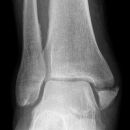

Maisonneuve

Sprunggelenk